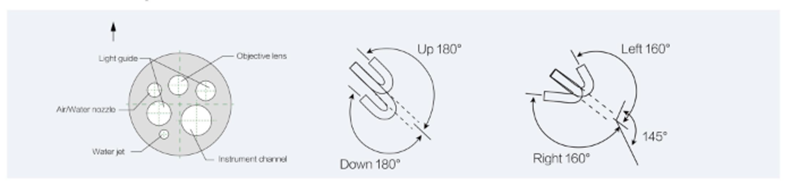

Video Colonoscope

Field of view | 120° | 145° | 145° | 145° | 145° |

Depth of view | 3-100mm | 3~100mm | 3~100mm | 3~100mm | 3~100mm |

Bending capability(UP/DOWN) | 180° /180° | 180° /180° | 180° /180° | 180° /180° | 180° /180° |

Bending capability(RIGHT/LEFT) | 160° /160° | 160° /160° | 160° /160° | 160° /160° | 160° /160° |

Distal end diameter | 10.8mm | 12.8mm | 12.8mm | 12.8mm | 12.8mm |

Insertion tube diameter | 10.8mm | 12.8mm | 12.8mm | 12.8mm | 12.8mm |

Instrument channel diameter | 3.2mm | 3.7mm | 3.7mm | 3.7mm | 3.7mm |

Working length | 1330mm | 800mm | 1330mm | 1550mm | 1700mm |

Water jet | Yes | Yes | Yes | Yes | Yes |